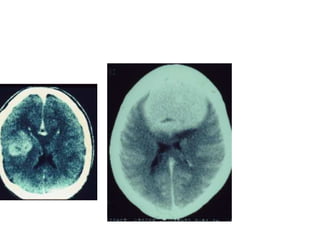

Vascular

Hemorragica

Isquemica

Neoplasica